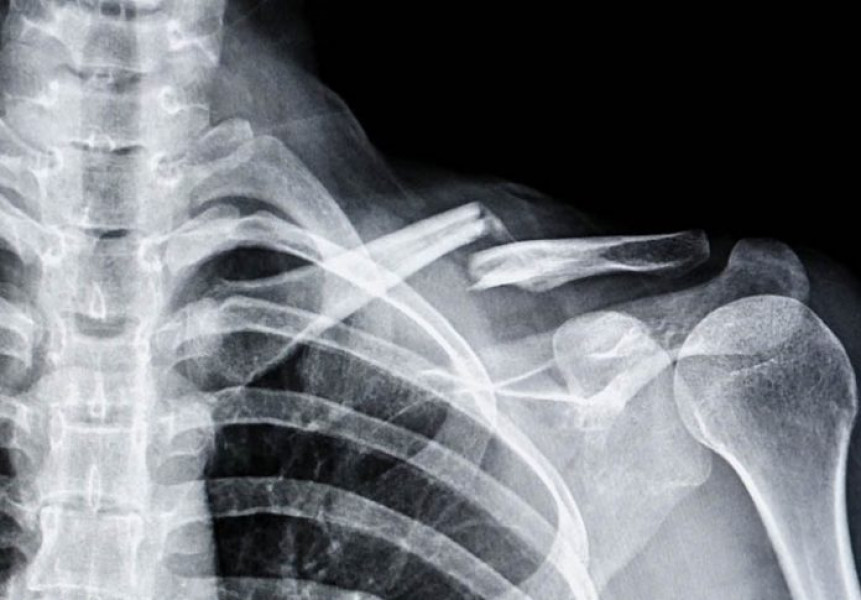

Cercetătorii din China au anunțat dezvoltarea unui adeziv osos inovator, numit „Bone-02”, care poate trata fracturile și fragmentele osoase zdrobite în doar trei minute. Această nouă substanță oferă o alternativă rapidă la metodele tradiționale chirurgicale.

Noua tehnologie promite să repare fragmentele osoase eficient și să reducă semnificativ nevoia implanturilor metalice sau a intervențiilor invazive complexe. Procedura cu adezivul „Bone-02” este considerată mult mai puțin traumatizantă pentru pacienți.